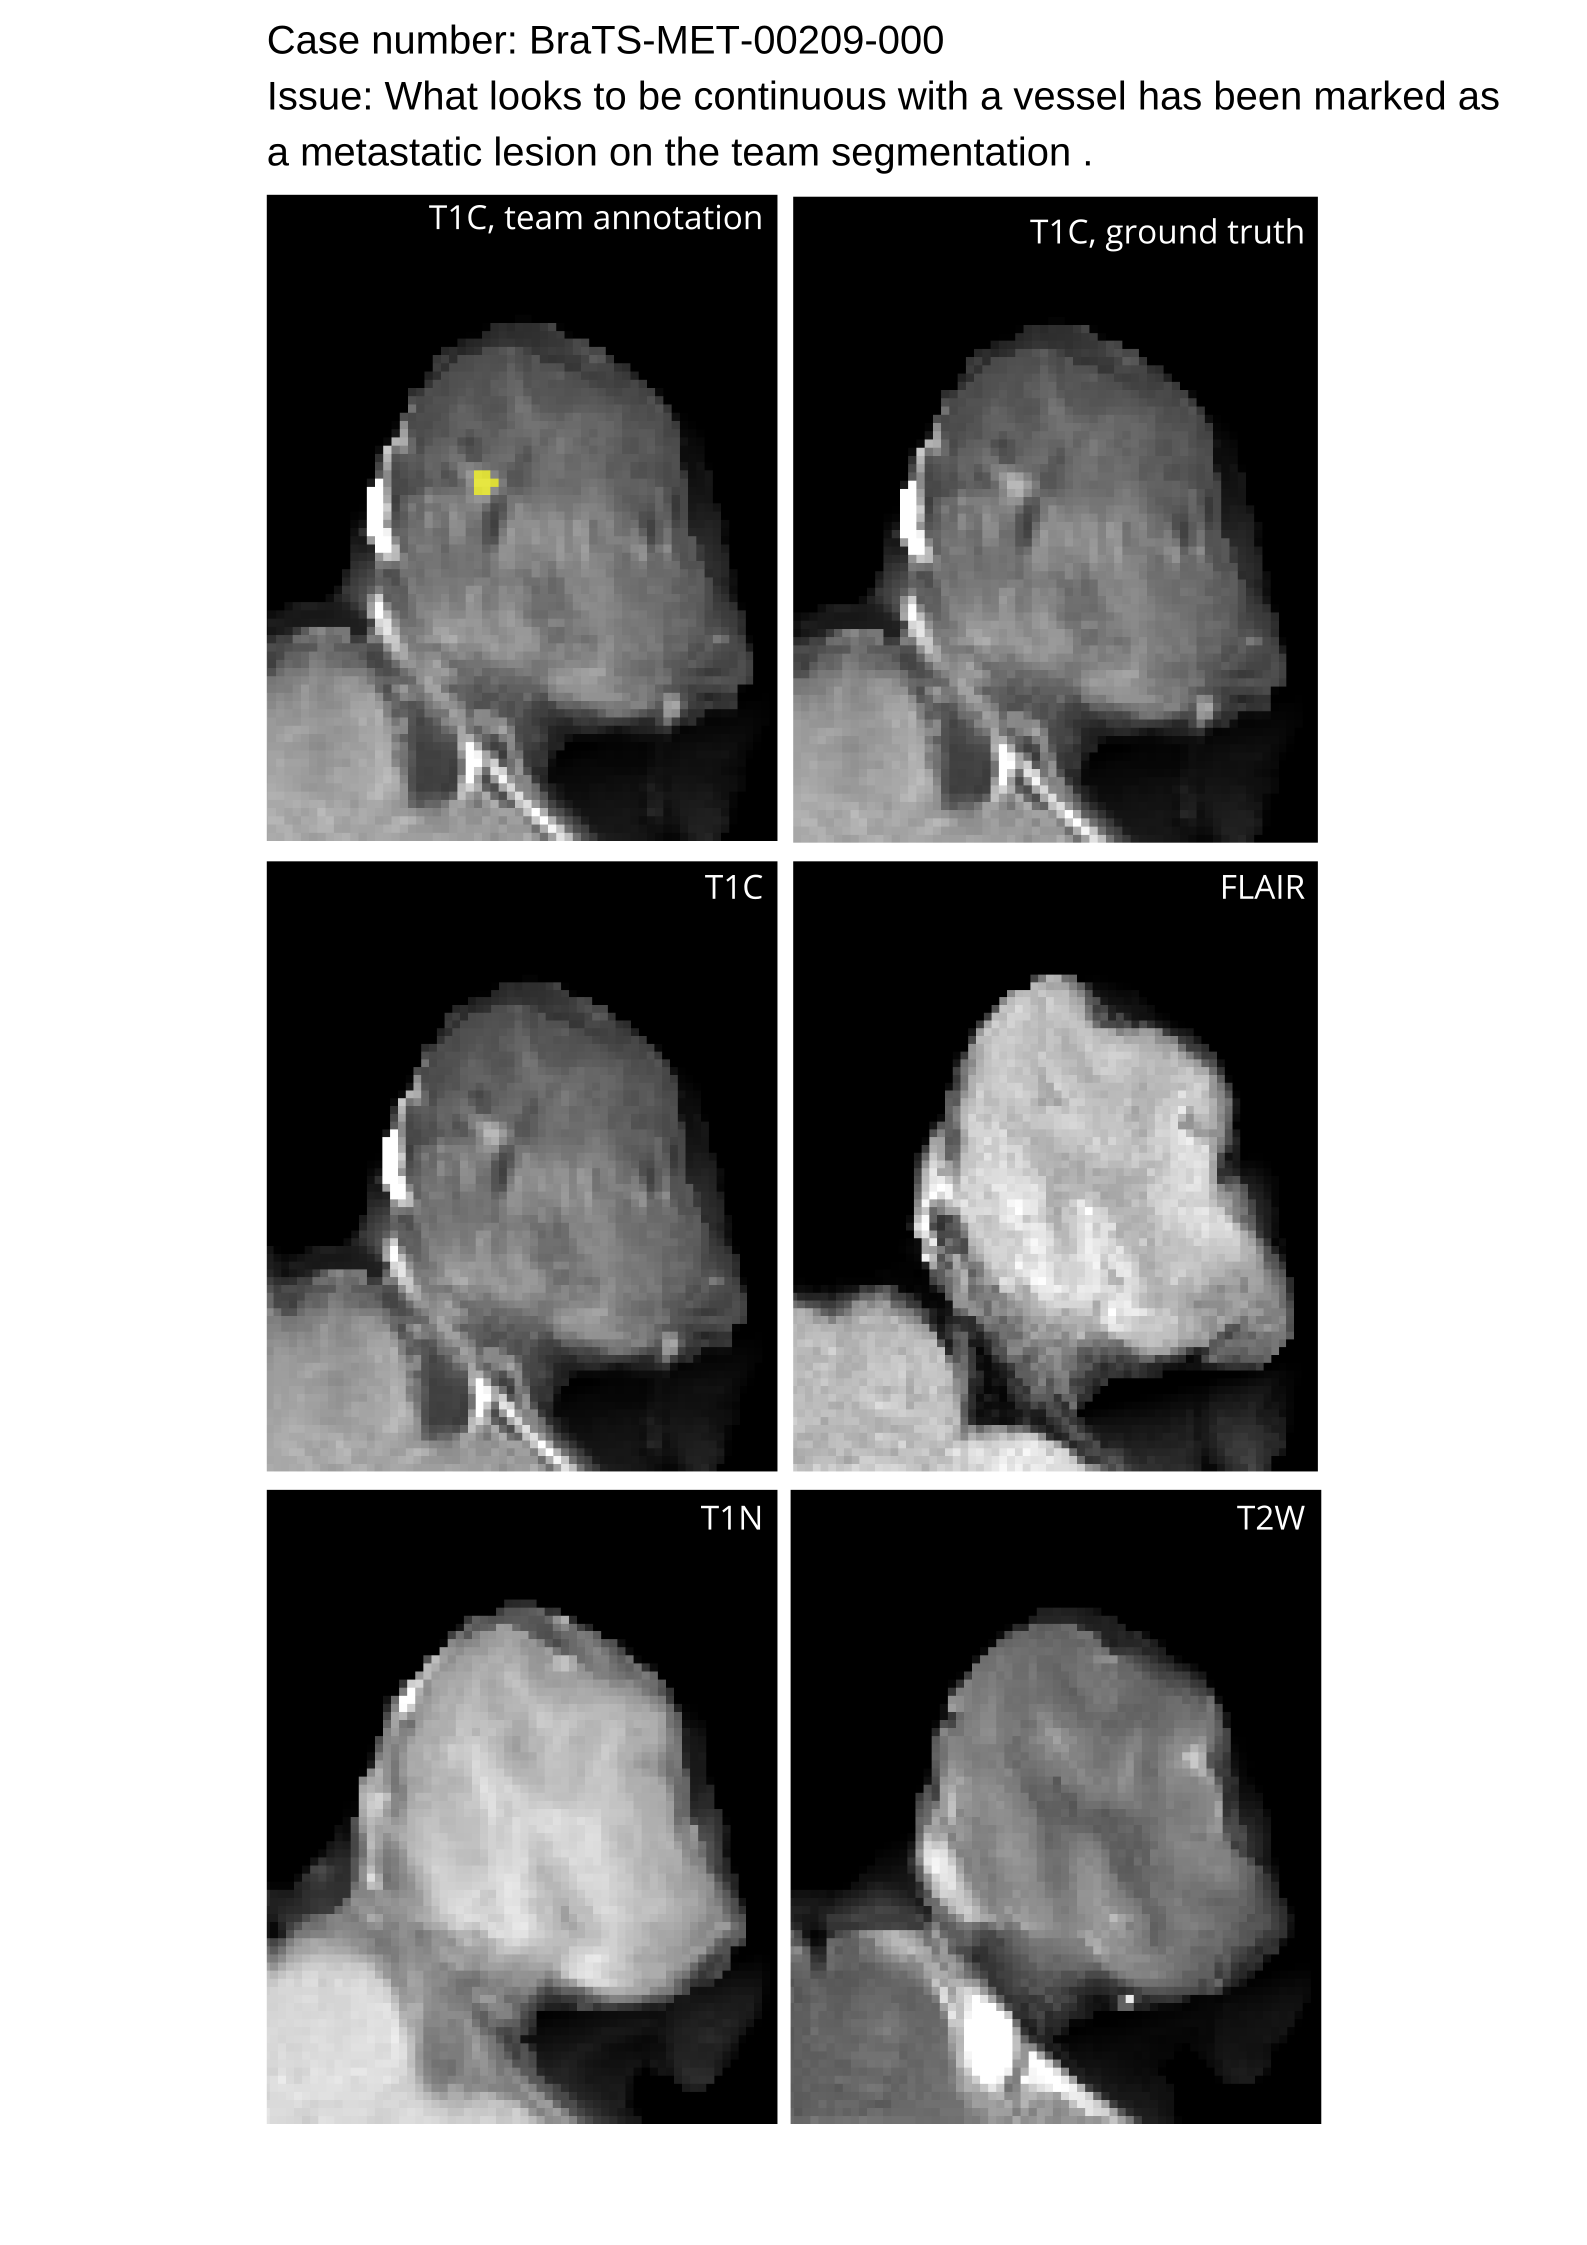

4.9 Common Errors of Automated Segmentations

Based on observations from previous BraTS challenges, common errors in automated segmentations were identified. The most typical errors in the current challenge included:

1. 1.

Automated algorithms missing small metastases. Enhancing metastasis was fused using the minority voting algorithm to aggregate all enhancing tumor voxels identified by the three algorithms. However, many small metastases were missed and were manually segmented by neuroradiology attendings.

2. 2.

Segmentation of white matter changes from microvascular disease. Peritumoral edema segmentations were checked by neuroradiology attendings and modified.

3. 3.

The segmentation of non-enhancing lesions that have intrinsic T1 hyperintensity. Voxels with intrinsic T1 hyperintensity were manually removed from ET segmentations.

These insights led to specific adjustments in the annotation process to enhance accuracy.